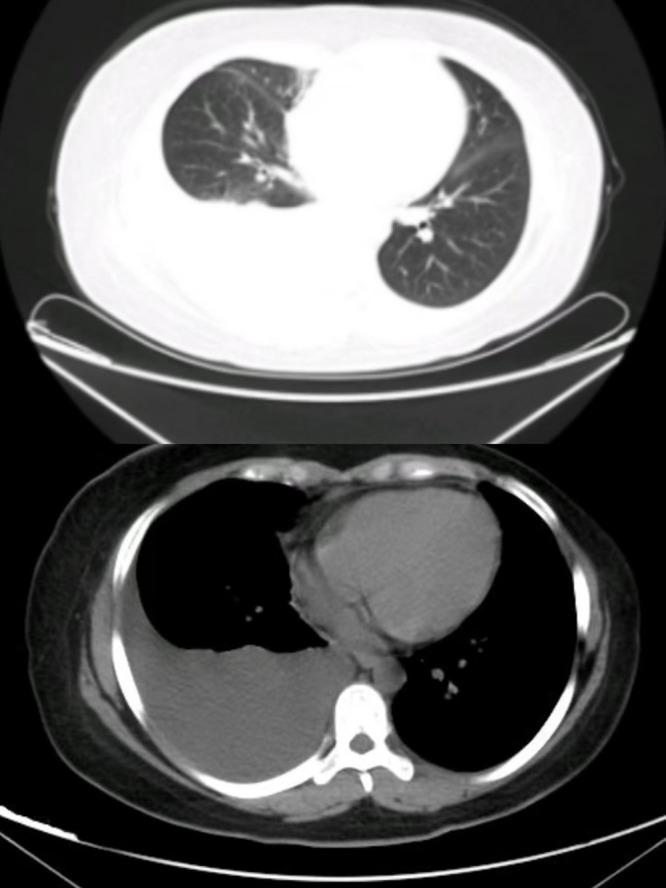

Tjalma's syndrome is a benign combination of ascites, pleural effusion, and elevated CA-125 occurring in patients with systemic lupus erythematosus. Reports of Tjalma's syndrome are scarce. An elevated CA-125 level often suggests the possibility of the presence of a malignant tumor. We report a case of generalised erythema and blisters with pruritus, massive unilateral pleural effusion and elevated CA-125. This patient was finally diagnosed with bullous systemic lupus erythematosus after exclusion of tumour and other maculopapular disorders. We hope that this particular case may provide a more comprehensive and novel diagnostic idea of systemic lupus erythematosus and pleural effusion, avoiding unnecessary anxiety, laboratory tests and surgical interventions.